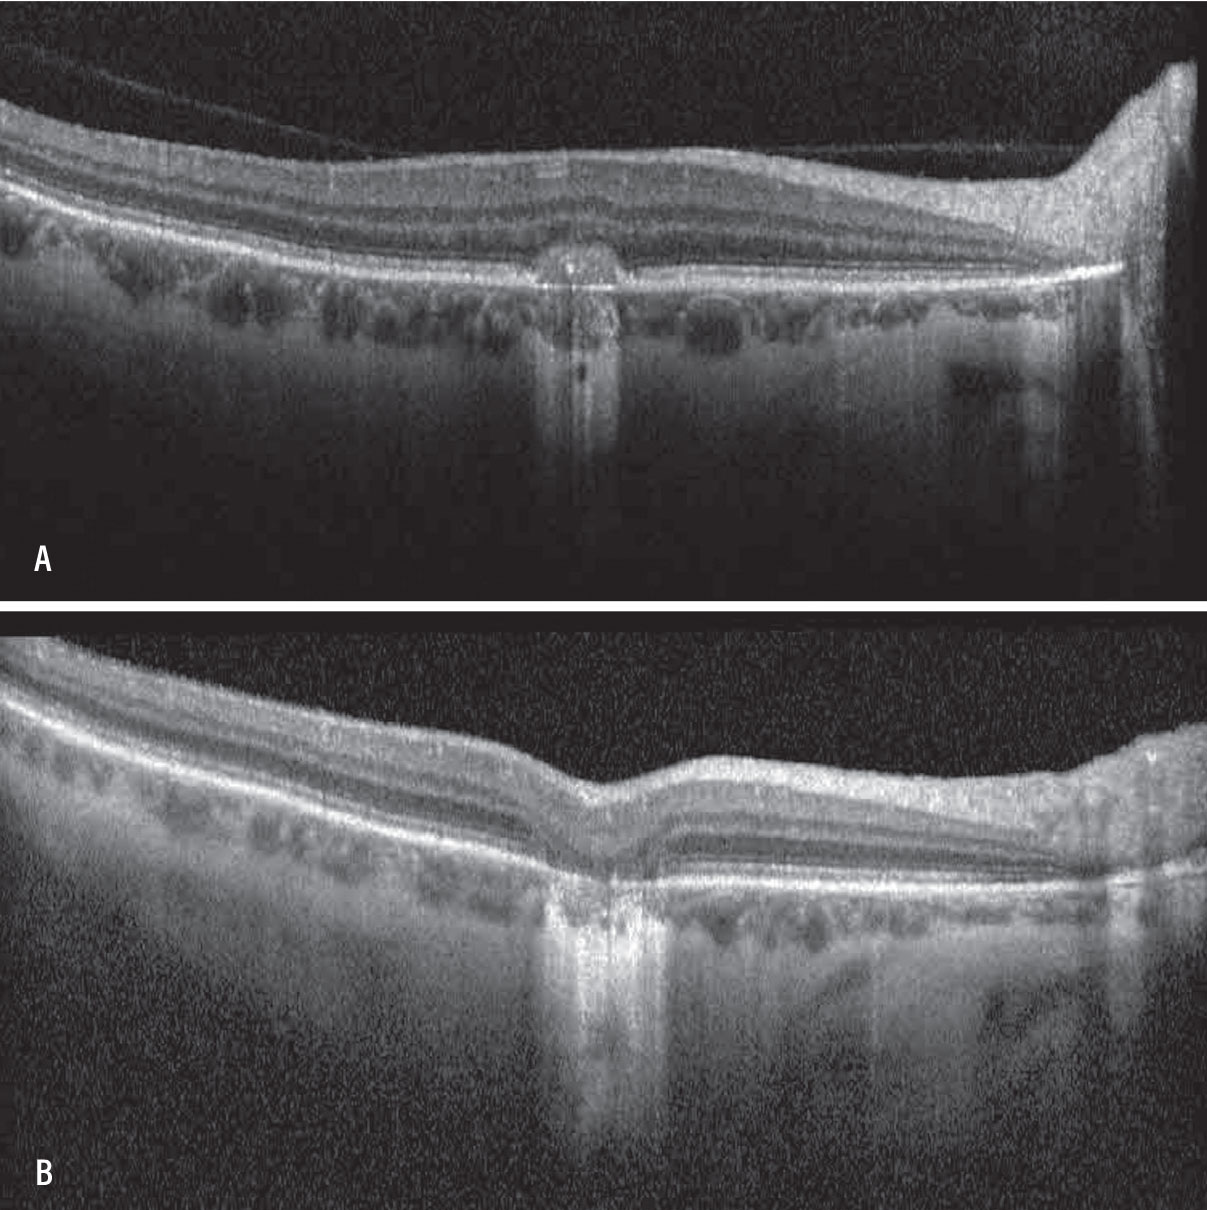

A) Optical coherence tomography of the macula of the right eye in a patient with a history of punctate inner choroidopathy showing classic choroidal neovascular membrane (CNVM). B) OCT of the macula of the right eye demonstrating resolution of CNVM and subsequent outer retinal atrophy after intravitreal anti-VEGF therapy. |

Inflammatory CNVM can be challenging to diagnose and differentiate from other entities. Uveitic cystoid macular edema can present with intraretinal fluid, subretinal fluid and outer retinal changes on optical coherence tomography that can make it difficult to distinguish from inflammatory CNVM, especially in patients with chronic inflammatory disease. Inflammatory CNVM often presents with subretinal hyperreflective material that can distinguish it from inflammatory CME.

FA can help distinguish between inflammatory pigment epithelial detachment and CNVM, which can often look similar. OCT angiography is another modality that can be helpful in making this distinction. However, in spite of these imaging modalities, differentiating between these two entities can still be difficult.